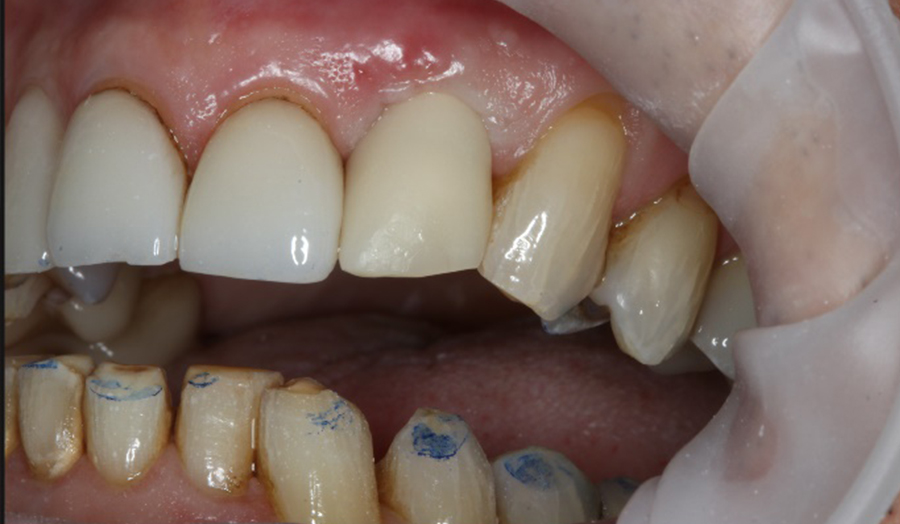

A 62-year-old male presented himself to my practice with a fractured non-restorable tooth #10. We planned a single implant with a surgical guide and a temporary bridge, both manufactured with Primeprint. The surgery was completed in 20 minutes, and it took us 10 minutes to bond the temporary bridge.

Before: Initial situation with a fractured non-restorable tooth #10